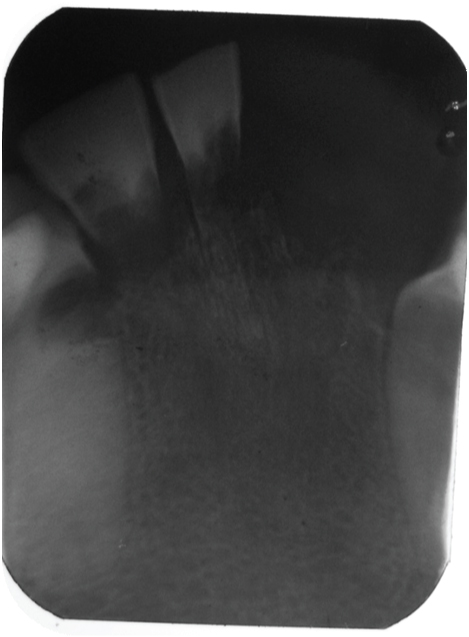

[Table/Fig-3] showing the normal morphology of crowns of the maxillary teeth. [Table/Fig-4] showing the normal morphology of crowns of the mandibular teeth. Full mouth intraoral periapical radiograph revealed complete root resorption in relation to 11, 12, 41 and 42; cervical resorption in 15, 33, 34 and 43, 44; apical resorption in 16, 24, 25 and 26. Resorption in both apical and cervical region was noticed in relation to 35, 36 and 46. Panoramic radiographs showed multiple ill defined radiolucent areas in apical third and cervical region of all teeth in varying degree. Lateral view of skull showed no evidence of any skull changes. In [Table/Fig-5] intraoral periapical radiograph showing complete root resorption in relation to 11 and 12. In [Table/Fig-6] intraoral periapical radiograph showing complete root resorption in relation to 41 and 42. In [Table/Fig-7] intraoral periapical radiograph showing cervical resorbtion in relation to 15 and apical root resorption of mesial and distal roots in relation to 16. Loss of PDL space in 17 can be appreciated.

Intraoral periapical radiograph showing complete root resorption in relation to 41 and 42